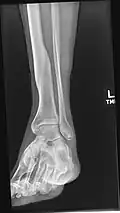

X-ray avulsion fracture of the summit of the left lateral malleolus.